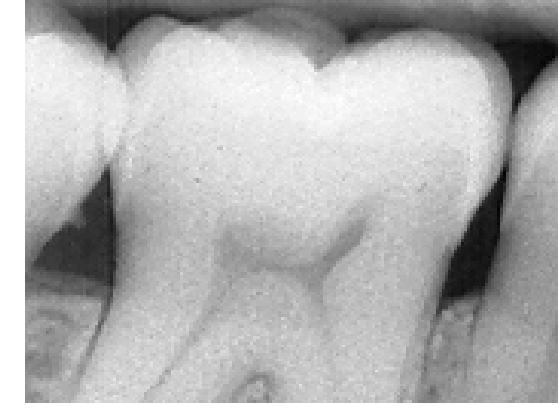

5.2.1 Multiclass high-quality bitewing X-ray image.

Our second scanned bitewing X-ray image shows a central molar tooth and partial views of its neighbor teeth, gums and background, Figure 9 (a). We have set three classes in this image to account for the differences between tooth enamel and dentin. Enamel is the thin, hard material that covers the dentin, or main body of the teeth, and protects it from harsh temperatures. We initialized both algorithms with automatic EM and supervised classification. In Figure 9 we can observe from the segmentations that, in the supervised case, (c), (d), (e), the teeth are correctly segmented, dentine is clearly differentiated from tooth nerve and enamel. Initializing with automatic EM, Figure 9 ((f), (g), (h), gives only a binary division, background from teeth and gum. In this example, PCVT makes a slightly better job than ICM, since the background is better separated from the teeth. The joint histogram of the image, Figure 9 (b), does show at least three distinctive modes; in Figure 10, the histogram shown in panel (a)corresponding to the X-ray image of an incisive, is flat. Its corresponding segmentations, shown in panels (c)-(f), made with four classes, do not distinguish well tooth enamel, dentin and background. In the expert’s opinion, PCVT is the only method that separates correctly enamel from background and dentin.